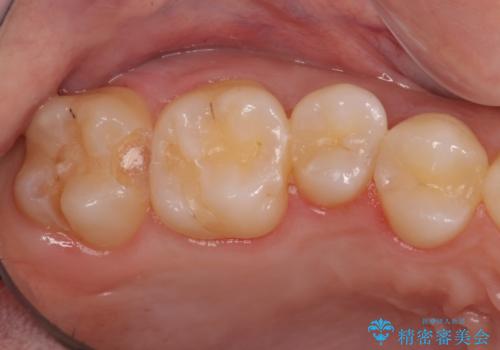

奥歯の虫歯治療でしたが、プラスチック周りと、歯と歯の間が大きな虫歯になっていました。

インレーでの修復予定でしたが、歯と歯の間が狭く、正確な型取りが難しい状態でした。